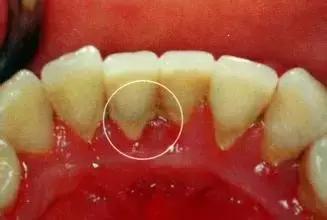

(1)龈上牙结石

位于龈缘以上的牙面上,肉眼可直接看到。在牙颈部沉积较多,特别是在大涎腺导管开口相对处,如上颌磨牙的颊侧和下颌前牙的舌侧沉积更多。龈上牙石中无机盐的主要来源是唾液中的钙、磷等矿物盐。